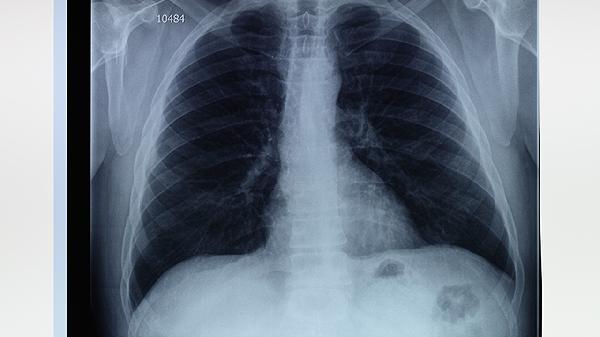

肺大泡患者需注意避免剧烈运动、预防呼吸道感染、戒烟、定期复查肺功能、保持健康体重。肺大泡是肺泡异常扩张形成的囊泡样病变,可能影响呼吸功能。

每6-12个月需进行肺通气功能检测和胸部CT复查,评估肺大泡大小变化及剩余肺功能。动态监测有助于早期发现气胸或新发病灶,医生可根据结果调整氧疗等干预方案。